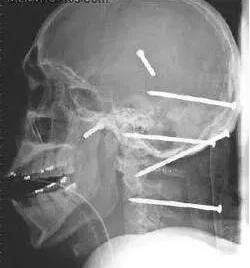

8—9个月以后饥饿的感觉逐渐下降,直至彻底消失。马克内认为,大部分人只利用了大脑的3%——10%,而他则利用了大脑能量的25%。他是唯一一个做到这一点并被医学界注意的人。科学家通过CT和MRI扫描发现这位64岁老人的松果体只相当于20岁的年轻人。